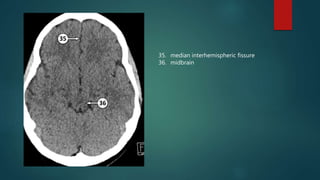

Presentation1.pptx, radiological anatomy of the brain. | PPTX

Radiological anatomy of brain.pptx